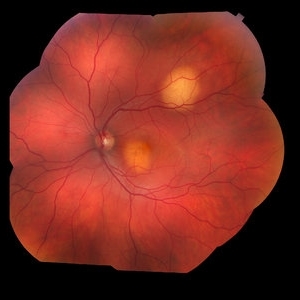

Ocular Parasitosis

Color fundus montage of an 12-year-old boy with ocular parasitosis affecting his left eye. Patient presented with decreased vision and recent travel to Florida. The specimen was lost in the lab and was never recovered.

Photographer: Olivia Rainey

Imaging device: Topcon 50dx

Condition/keywords: color fundus photograph, color photo, intraocular foreign body, left eye, montage, parasite